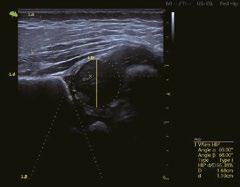

Intelligente Erfassung und Stadieneinteilung von Schilddrüsenerkrankungen

Schilddrüsenknoten werden in Echtzeit oder auf gespeicherten Bildern erkannt, zusammen mit dem T-RADS-Kategorisierungs- und Berichtstool, wodurch die klinische Routine der Schilddrüsenultraschalluntersuchung genauer und aussagekräftiger wird.

Intelligente Erfassung und Stadieneinteilung von Brustkrankheiten

Das automatische Brustscreening und die Erkennung von Läsionen in Echtzeit oder auf gespeicherten Bildern verbessert zusammen mit der intelligenten Bl-RADSAnalyse die Qualität der Kontrolle nachhaltig.